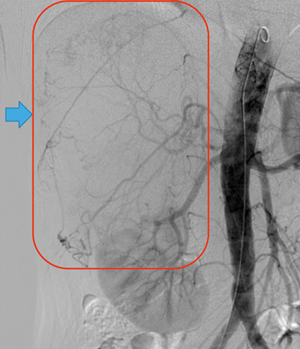

右副腎腫瘍摘出の栄養血管推定術前シミュレーションとして,造影CT,腹部アンギオを行った。アンギオの結果,副腎腫瘍には右横隔膜下動脈,右肝動脈からの分岐右副腎動脈,腰動脈などから多数の栄養が認められた(図1)。さらに,右腎動脈遠位付近より副腎腫瘍に上行する血管を確認したため,右腎動脈を選択造影したが(図2),どこから分岐しているのかアンギオ,造影CTのVR処理,MIP画像,MPR画像のいずれでも推定が困難であった(図3,4)。

図1 腹部大動脈造影画像(上腸間膜動脈レベルより造影) |

図2 右腎動脈の選択造影画像 |